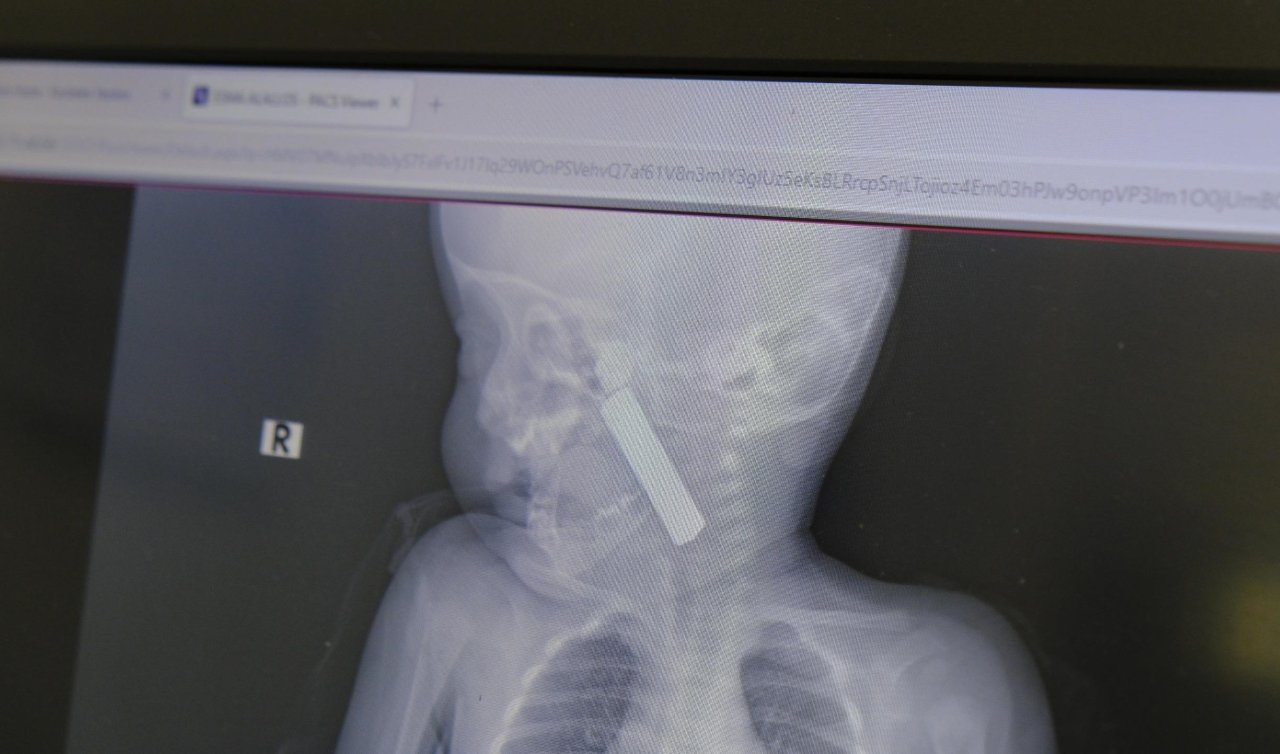

Yapılan incelemede Türkan Abay'ın sol karın ve göğüs bölgesinde 17, yüzünde 3, boynunun sol kısmı ve sol kolunda 2'şer ve köprücük kemiğinde 1 olmak üzere 25 bıçak darbesi belirlendi. Abay'ın cenazesi incelemenin ardından Antalya Adli Tıp Kurumu'na gönderildi. Şüpheli Abdüsselam Abay Cinayet Büro Amirliği ekipleri tarafından evde gözaltına alınırken, olayda kullanılan bıçağa ise el konuldu.